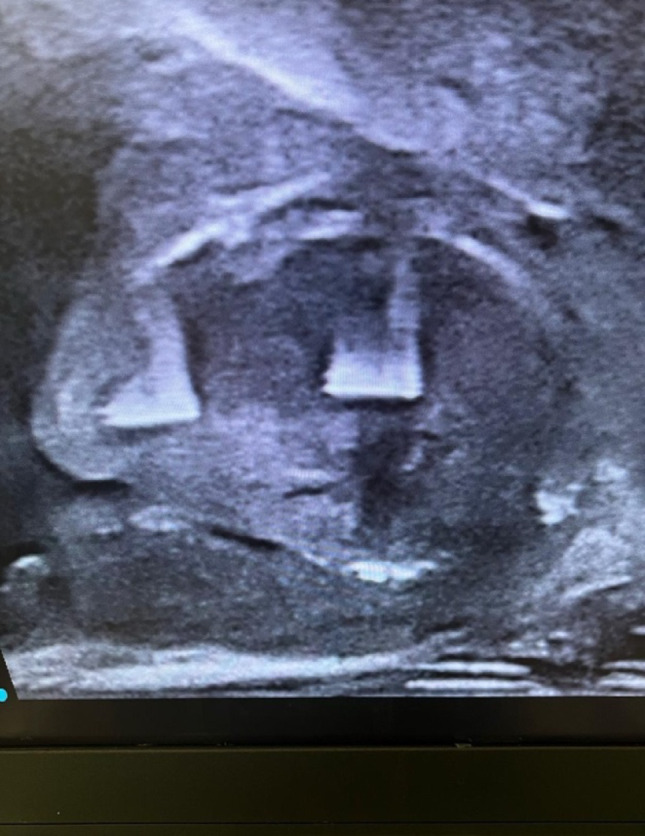

Results: The study included 40 patients with a mean age of 68 (SD ± 8.91) years with moderately enlarged prostates (mean volume 81.56 mL, (SD ± 25.32), and median PSA 3.2 ng/dL). Five patients were presented initially with an indwelling Foley catheter, so their data were not included in the statistical analysis. After Aquablation, the mean IPSS improved from 24.7 (SD ± 7.63) at baseline to 9.8 (SD ± 2.55) (p < 0.0001), the mean Qmax increased from 9.6mL/sec (SD ± 5.76) at baseline to 20.8mL/sec (SD ± 6.28) (p < 0.0001), and the mean PVR decreased from 143mL (SD ± 104.89) at baseline to 36mL (SD ± 30.63 ) (p < 0.0001). The hospital stay for patients admitted ranged from 1 to 2 days. Moreover, there were no major intraoperative difficulties removing dislodged Urolift clips with a loop resectoscope at the end of the procedure, while non-dislodged clips were left in situ. None of the patients had postoperative bleeding that required hospital admission or blood transfusion following discharge.

Abstract Image